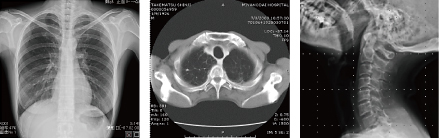

さまざまな撮影画像を診断目的や症例内容に応じて調整することで、モニターによる画像診断をサポートします。

医療クラウドサービスの画像解析オプションをご利用いただくことができます。画像解析機能によって、画像診断を強力にサポート。

- *2 本サービスは胸部X 線画像病変検出(CAD)プログラム LU-AI689 型で実現しています。